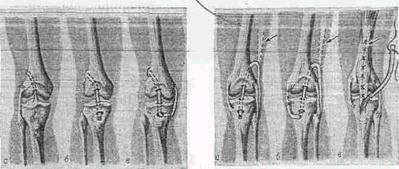

Рис 1.1. Операции на коленном суставе

Рис 1.2. Схема пластики крестообразных и боковых связок

Различают продольный, косопоперечный, поперечно полный и неполный разрыв менисков, отрыв переднего или заднего рогов его и полный отрыв мениска от капсулы сустава и коллатеральной связки, или паракапсульный разрыв мениска (рис.9а, 9б).

Рис. 9а Вариант разрыва медиального мениска правого коленного суставе; 1 - полный поперечный разрыв; 2 - продольный неполный отрыв переднего рога; Рис 9б Отрыв медиального мениска правого коленного сустава от капсулы (1), и продольный разрыв внутреннего мениска.